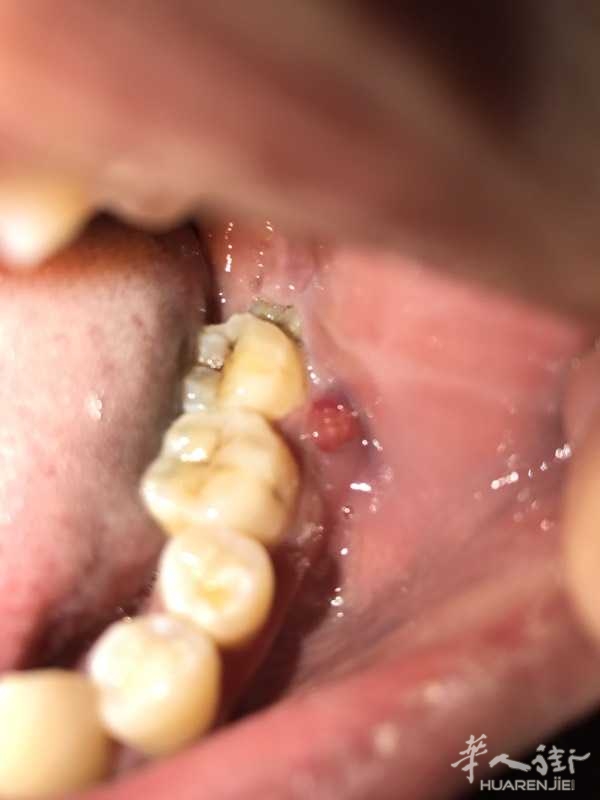

[寻医问药] 长智齿引起嘴巴里起了个水泡,反复出脓怎么办

长智齿引起嘴巴里起了个水泡,反复出脓怎么办

已经吃了一个多礼拜的消炎药不见好